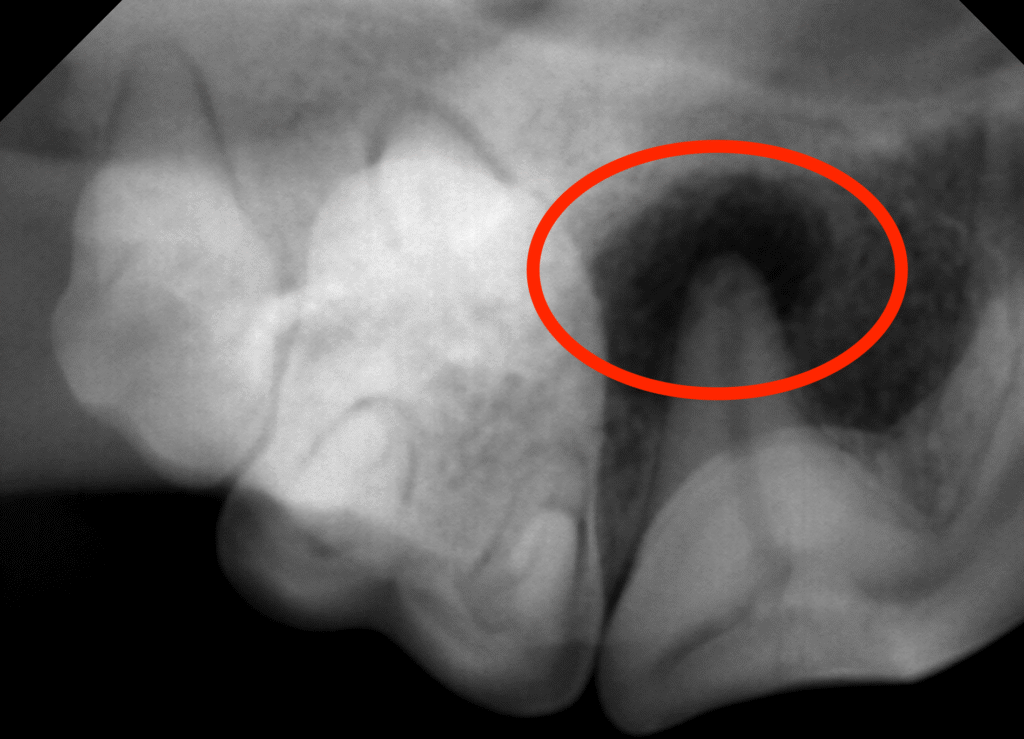

また口腔内X線検査では尾側根周囲に明らかな骨吸収像が認められたことから露髄からの細菌感染による根尖病変と考えられました。